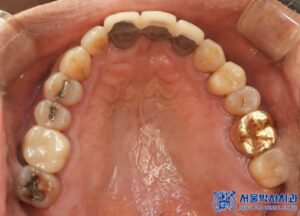

위 환자분께서는 오랫동안 없던 어금니뿐만 아니라

나머지 불편한 치아들도 함께 치료를 원하셨는데요.

또한, 다른 치아들의 충치와 손상된 부위에 대해서도

신경치료와 보철 치료를 함께 진행하며,

전반적인 구강 건강을

회복할 수 있도록 도와드리기로 하였습니다.

임플란트 치료 외에도, 환자분의 남아있는

치아들 중 심한 충치가 있는 어금니

(오른쪽 위 큰 어금니, 왼쪽 위 작은 어금니,

왼쪽 위 큰 어금니, 왼쪽 아래 큰 어금니)는

신경치료를 진행하였습니다.

신경치료가 끝난 어금니는 치아를 보호하기 위해

크라운 치료를 진행하였습니다.

추가적으로, 충치 범위가 크지 않은 송곳니와

작은 어금니는 레진 치료를 진행하였습니다.